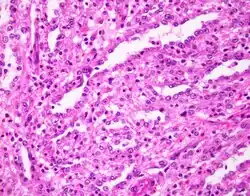

| Collecting duct carcinoma. H&E stain. | |

Histologic examination of collecting duct carcinoma demonstrates an infiltrative lesion with tubulopapillary, irregular channels lined by high grade hobnail cells with marked desmoplastic response and brisk neutrophilic infiltrate.